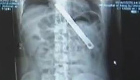

4年前,北京阜外医院救治了一名患有先天性心脏病的婴儿。手术成功了但孩子声门狭窄,父母说是医院造成的,于是把孩子留在医院就没再回来。日前,此案被强制执行,孩子见到妈妈第一句话竟是:“阿姨好”。